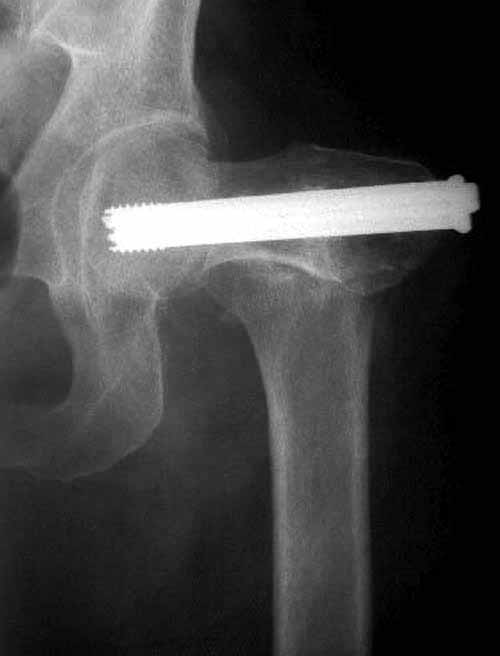

Работа Burstein AH and Wright TM: Fundamentals of Orthopaedic Biomechanics. Williams & Wilkins, Baltimore, pp. 160-169, 1994 доказывает, что шурупы, введенные на уровне малого вертела или ниже, приводят к осложнению. Введенные шурупы под 135 и больше градусов в 20% осложнились подвертельными переломами бедра.

Здесь подобный случай, где стрессовый перелом обнаружен через 2 недели после фиксации. Применен Blade Plate с дополнительными шурупами.